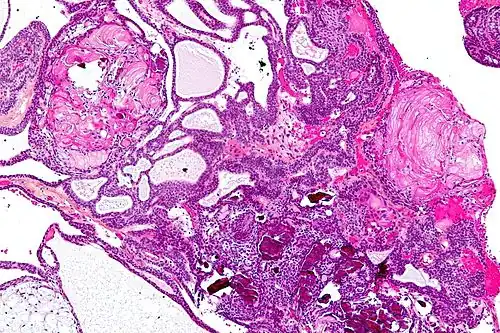

Very low magnification micrograph of an adamantinomatous craniopharyngioma. HPS stain. | |

On macroscopic examination, craniopharyngiomas are cystic or partially cystic with solid areas. On light microscopy, the cysts are seen to be lined by stratified squamous epithelium. Keratin pearls may also be seen. The cysts are usually filled with a yellow, viscous fluid rich in cholesterol crystals. Of a long list of possible symptoms, the most common presentations include headaches, growth failure, and bitemporal hemianopsia.

Micrograph showing the characteristic features of an adamantinomatous craniopharyngioma - cystic spaces, calcifications, and "wet" keratin, HPS stain